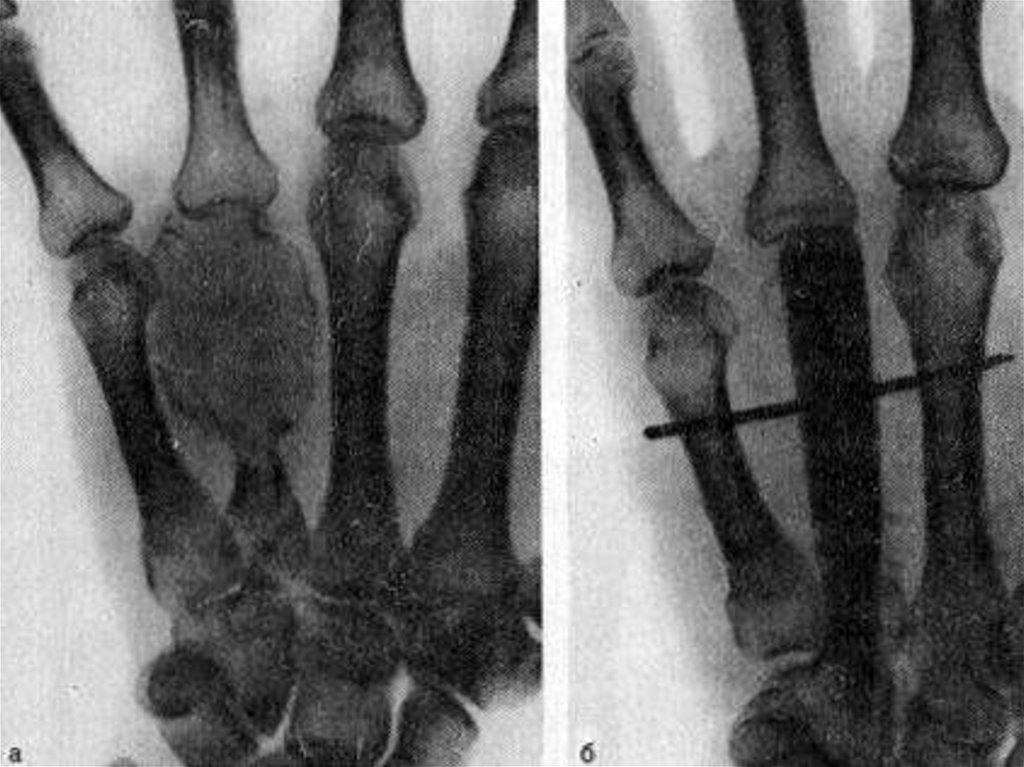

11. Диагностика Остеобластокластомы

После физикального осмотра для уточнения диагноза

доктор, как правило, рекомендует необходимое

обследование, которое включает:

• рентгенологическое исследование (выявляется

булавовидное «вздутие» контуров кости, неравномерное

истончение и разрушение кортикального слоя, при

ячеистом варианте появляется перестройка костного

губчатого вещества, напоминающая густую сетку,

литическая остеобластокластома отличается сплошными

деструктивными очагами, четко разграниченными от

нормальной кости)

16. Лечение

Лечение остеобластокластомы – оперативное,

хирургическое. Операция может проходить согласно

одной из трех, в зависимости от стадии развития,

стандартных методик.

Самая щадящая операция проходит на начальных

этапах развития опухоли данного вида, проходит с

помощью вылущивания полости кисты с последующим

заполнением ее костной тканью. Костная ткань для

заполнения берется из другой здоровой кости пациента.

Кроме того, что такая операция наименее агрессивная и

травматичная, она все же имеет меньшую надежность,

чем другие два вида операций.

17.

Более радикальная операция –

иссечение пораженной части кости

вместе с кистой. При такой операции

вероятность рецидива сводится к